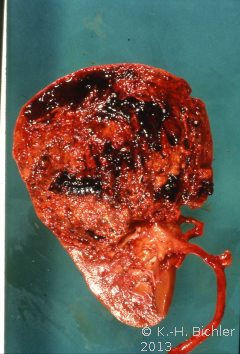

Makroskopisch zeigt der Tumor eine gelborange Farbe und ist durch Einblutungen und weißliche, Nekroseherde gesprenkelt. Außerdem finden sich Zysten von Millimeter- bis Centimeter-Größe (Abbildung 1). Auffällig häufig enthält das Nierentumorgewebe Kalzifizierungen. Zumeist ist der Tumor mehr oder weniger gekapselt und dadurch vom Nierenparenchym abgetrennt (s. Abbildungen Kasuistiken).